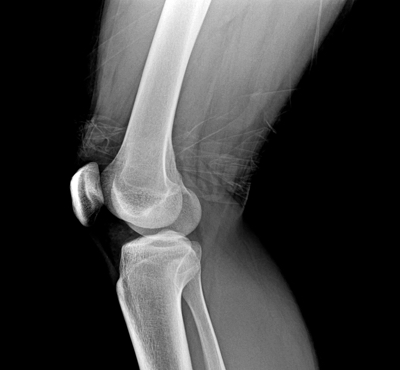

TG-C, our lead product candidate developed for the treatment of osteoarthritis (OA) of the knee, has completed Phase II trials in the U.S.

TG-C has the potential to become the first cell and gene therapy to effectively treat OA. Clinical trials conducted in the U.S. have demonstrated significant improvements in pain relief and joint function over a two-year period, along with indications of slowed disease progression of OA and structural joint improvements. As an allogeneic (off-the-shelf) therapy, TG-C may offer an alternative to conventional treatments and surgical interventions, or delay the progression of OA to minimize the need for multiple surgical interventions.

The Company has completed enrollment in its U.S. Phase III clinical trials, which are being conducted under a Special Protocol Assessment (SPA) agreement with the U.S. Food and Drug Administration (FDA). The trials are currently in the two-year follow-up period. The studies are designed to demonstrate and confirm TG-C’s efficacy in improving pain and function, and to support a potential designation as a disease-modifying osteoarthritis drug (DMOAD), which could make TG-C the first therapy to receive such a label from the U.S. FDA.

With the continued growth of the OA market globally, there remains a critical need for advanced therapeutic options that can halt or slow disease progression. Current treatments primarily focus on symptom relief and are generally limited in duration and impact. In developing TG-C, Kolon TissueGene aims to introduce a disease-modifying osteoarthritis drug (DMOAD) that may offer an alternative to conventional therapies and surgical interventions, or delay OA progression to reduce the need for repeated procedures.

Kolon TissueGene is committed to improving OA-related pain and knee function, while also demonstrating structural benefits within the joint to interrupt the cycle of inflammation and cartilage degradation.

The Company has completed enrollment in two pivotal Phase III clinical trials in the U.S. These trials are currently in the two-year follow-up period and are designed to confirm TG-C’s efficacy in improving pain and function. Additionally, the Phase III program includes image biomarker assessments to evaluate structural progression, supporting the Company’s objective to seek a DMOAD designation for TG-C—potentially making it the first therapy to receive such a label from the U.S. FDA.